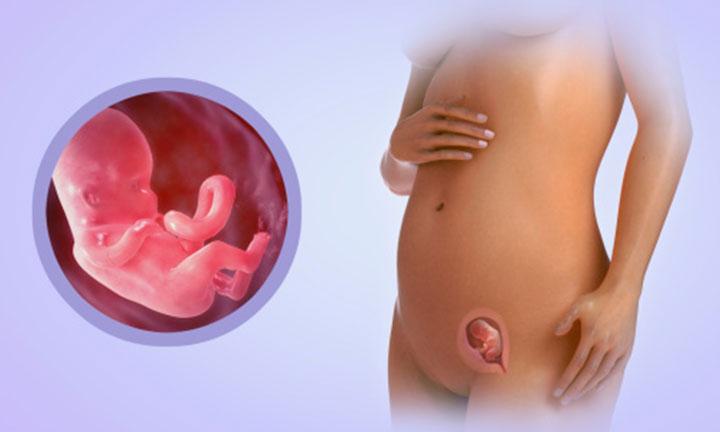

Этапы беременности: иллюстрации и развитие

Раздел: Лаборатория идей